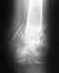

Похоже на несращение. Хотя для уточнения надо и посмотреть пацинтку, и сделать снимки в других проекциях. Если нет сращения, и есть болезненные проявления - лучше сделать остеосинтез. Можно обратиться в институт травматологии, к нам в отделение (Московская, 12) с 9 до 14 в рабочие дни. Паспорт, полис и снимки захватите.